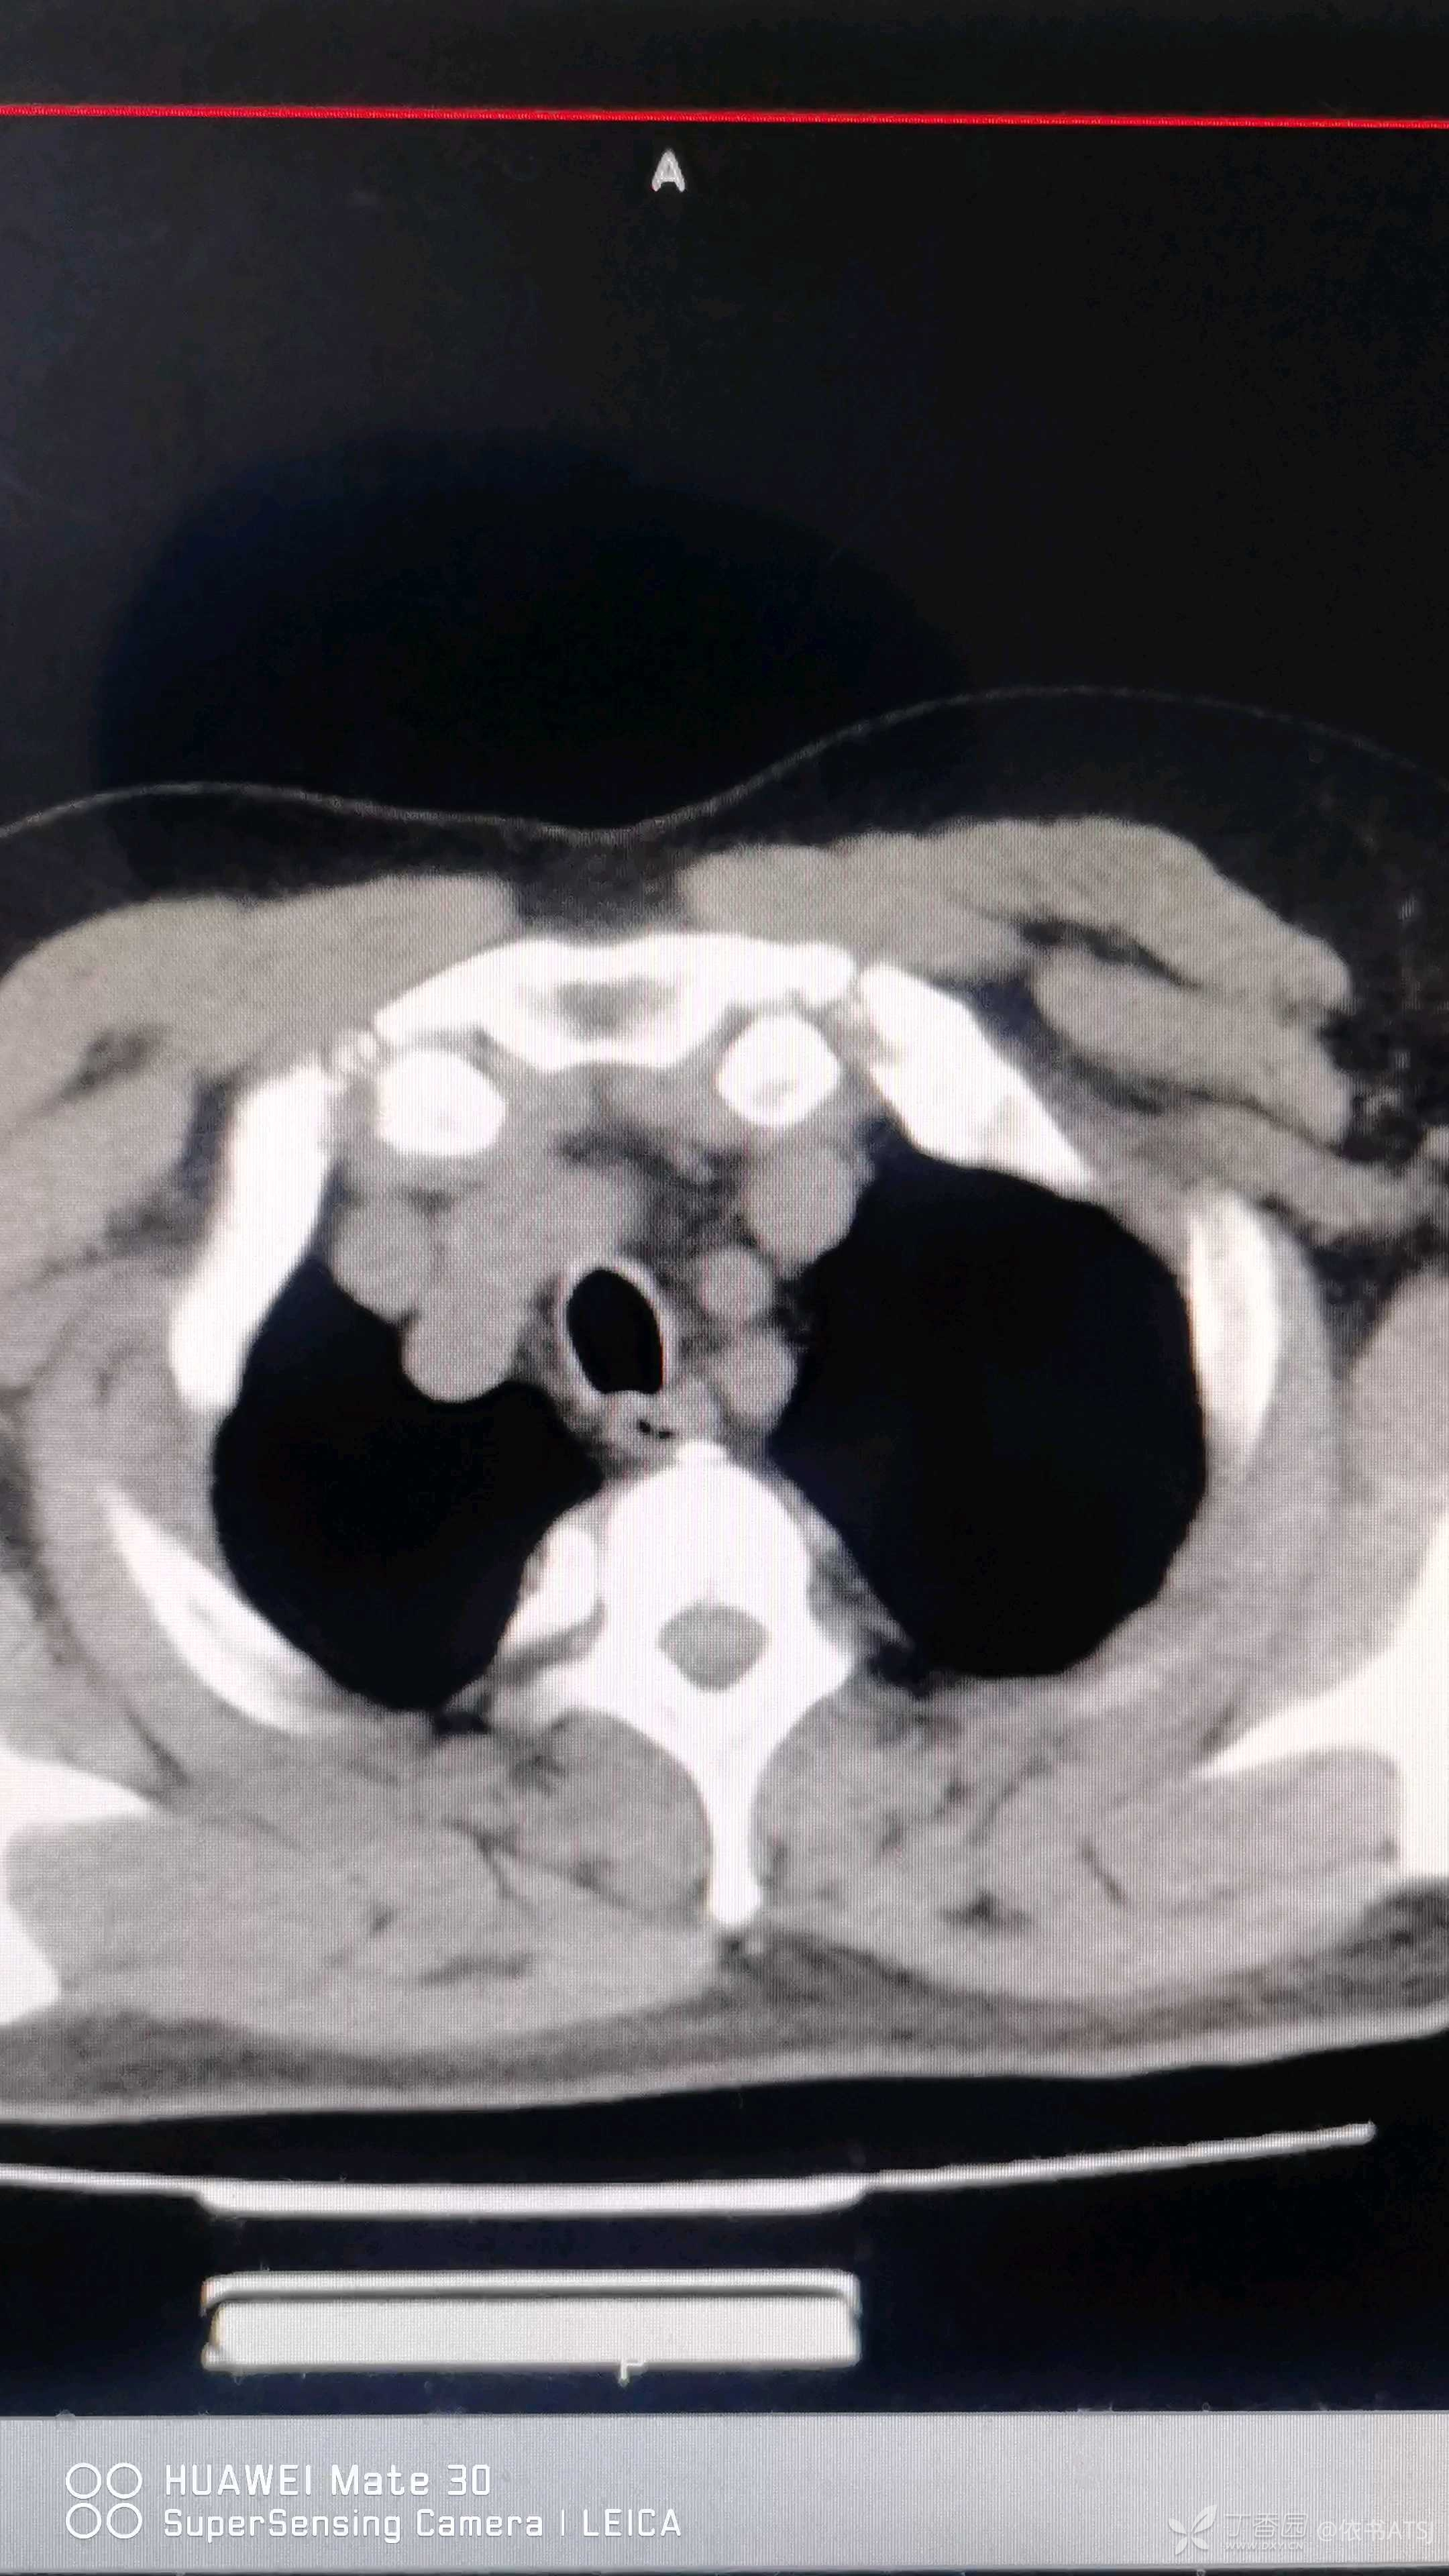

主动脉弓局限性外凸,密度不均匀,考虑溃疡形成,这个主动脉弓外凸的那个包,因溃疡形成,是个极度危险的信号啊!

大家看看主动脉弓的地方,有溃疡,有凸出,就是主动脉弓鼓了个包!